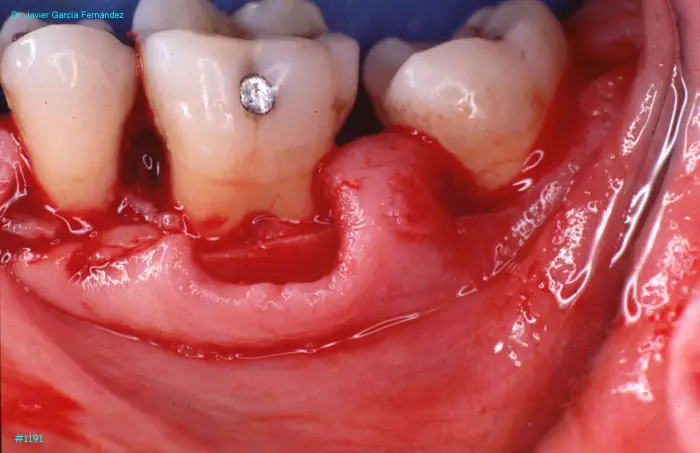

Atlas of Surgical Techniques in Periodontics. Chapter III. Atlas de Técnicas Quirúrgicas en Periodoncia